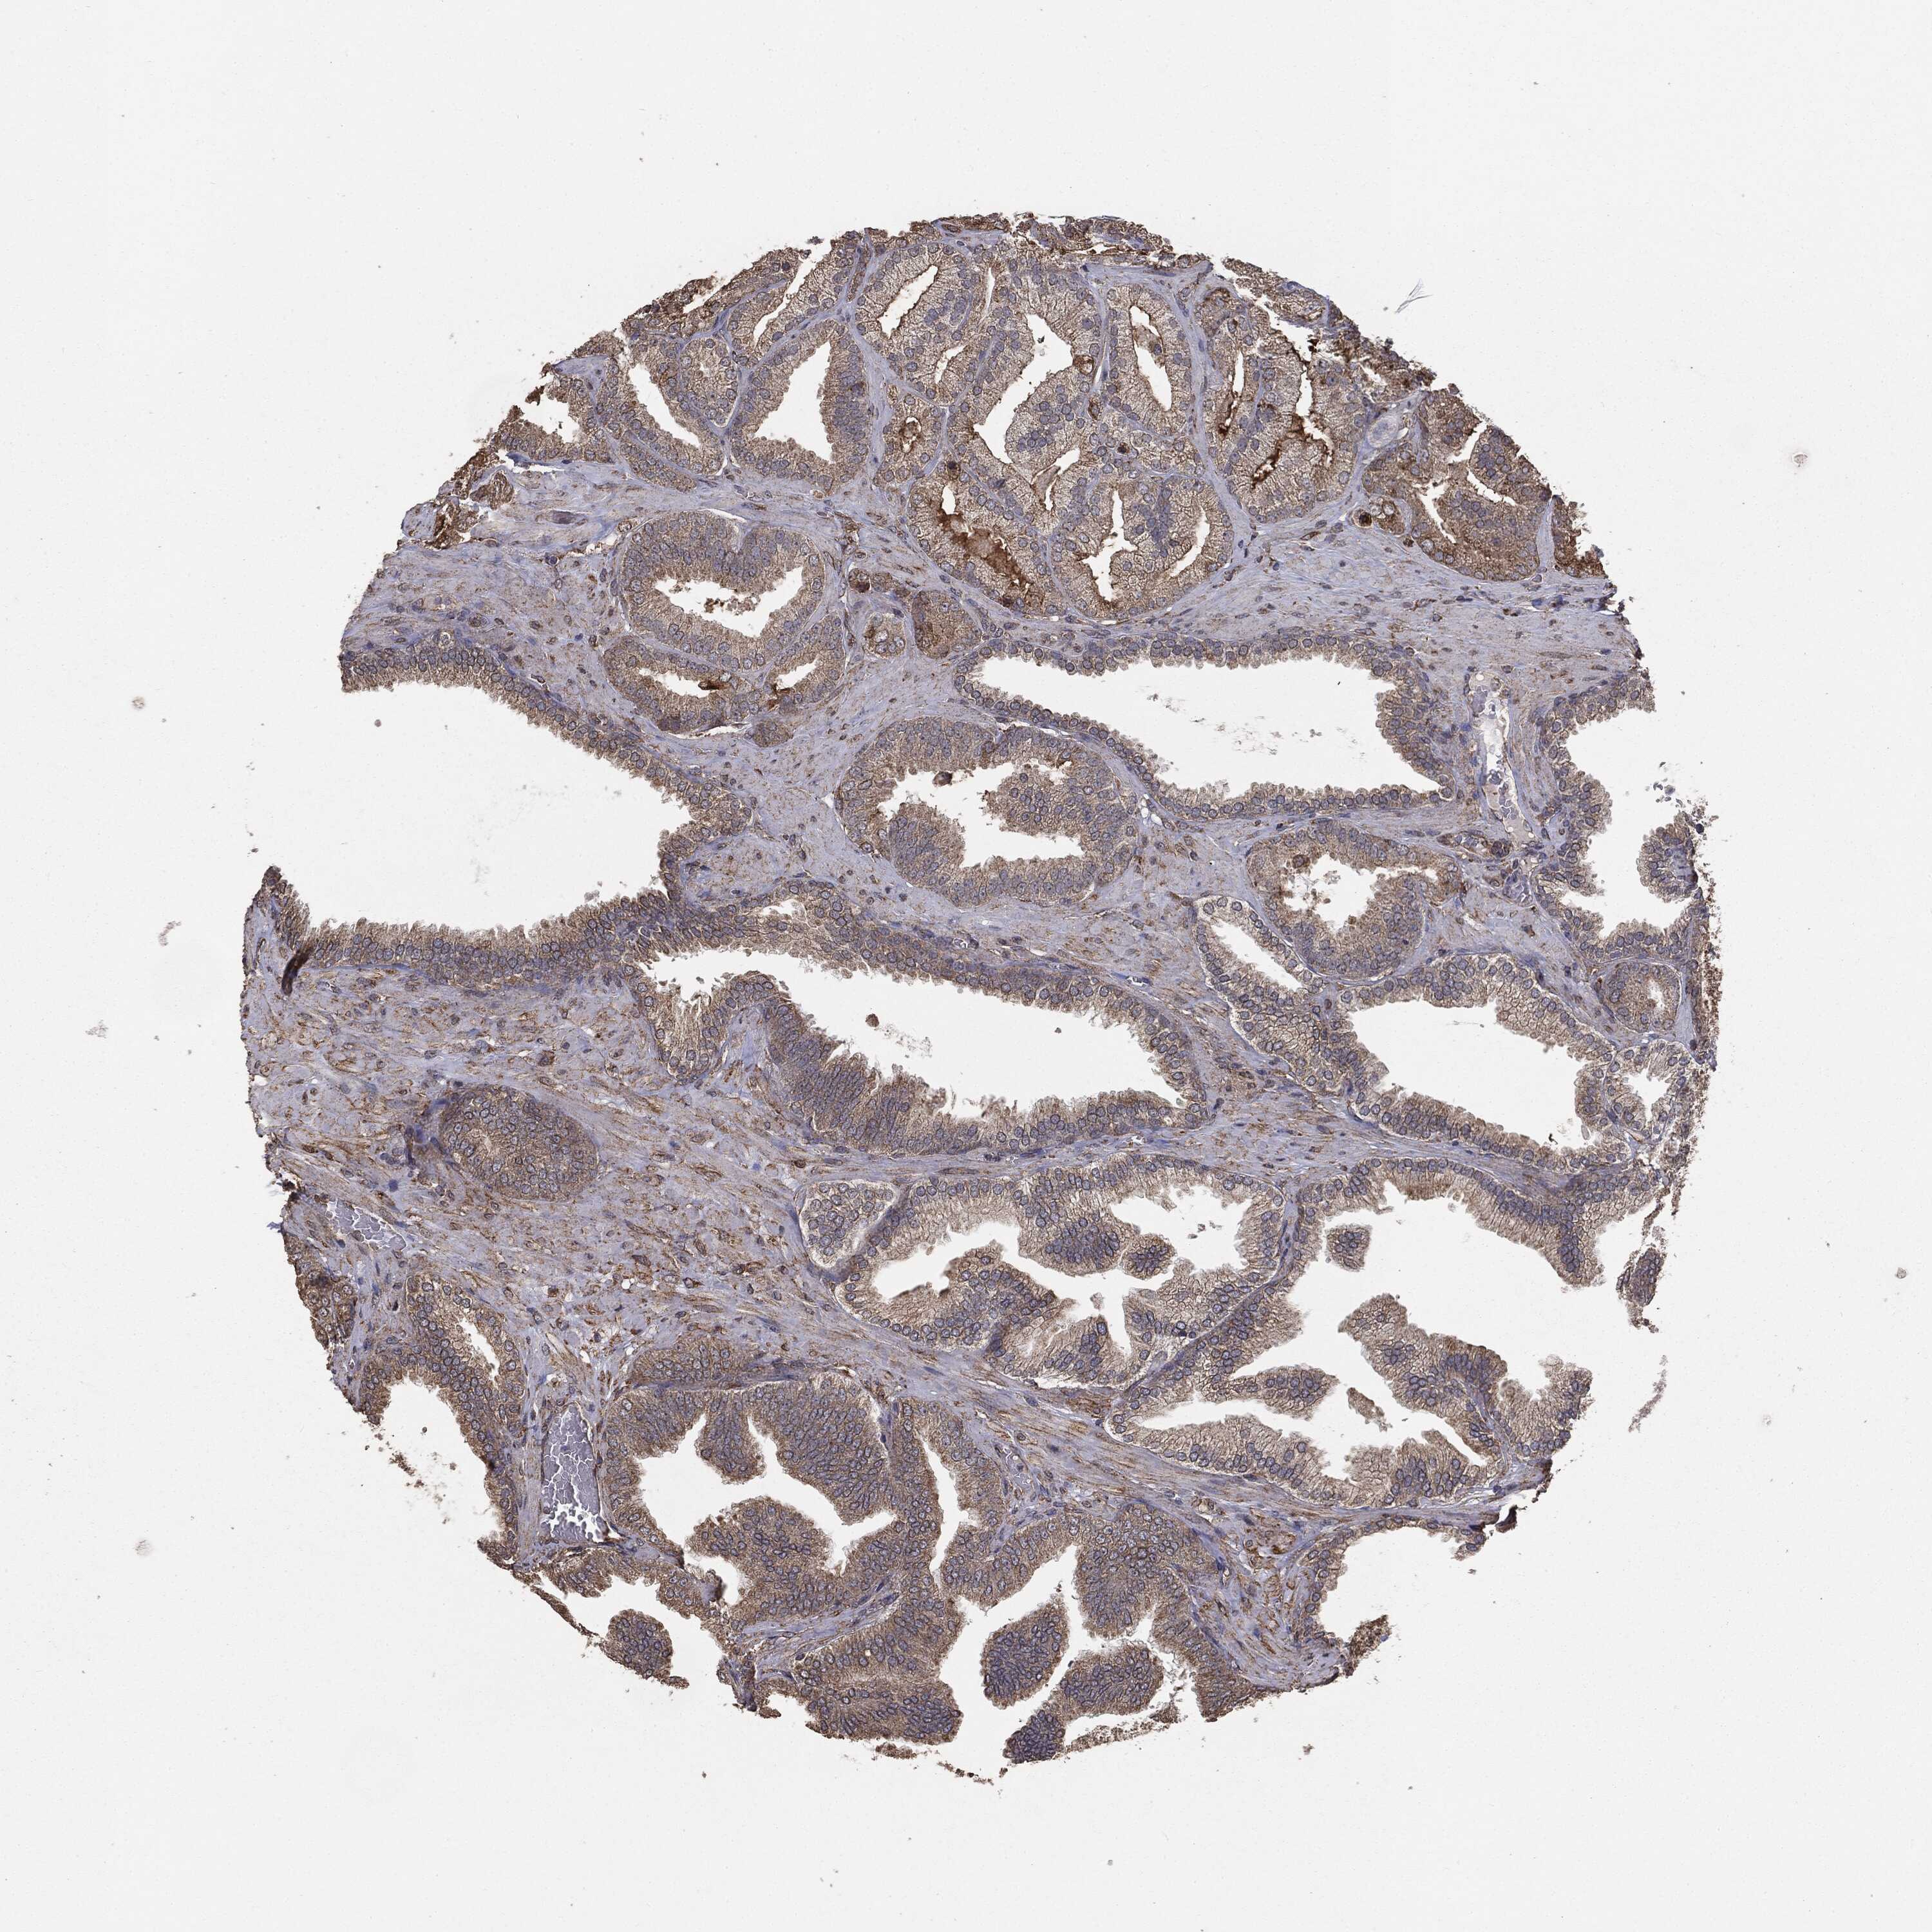

PROSTATE CANCER - Protein expressioni

A mouse-over function shows sample information and annotation data. Click on an image to view it in a full screen mode. Samples can be filtered based on level of antibody staining by selecting one or several of the following categories: high, medium, low and not detected. The assay and annotation is described here.

Note that samples used for immunohistochemistry by the Human Protein Atlas do not correspond to samples in the TCGA dataset.

Antibody stainingi

Antibody staining in the annotated cell types in the current human tissue is reported as not detected, low, medium, or high, based on conventional immunohistochemistry profiling in selected tissues. This score is based on the combination of the staining intensity and fraction of stained cells.

Each image is clickable and will lead to virtual microscopy that enables deeper exploration of all samples and also displays staining intensity scores, fraction scores and subcellular localization as well as patient and tissue information for each sample.

CAB069425

CAB080053

CAB080065

CAB080070

CAB080081

CAB080095

CAB080097

Staining

High

Medium

Low

Not detected

Intensity

Strong

Moderate

Weak

Negative

Quantity

>75%

75%-25%

<25%

None

Location

Nuclear

Cytoplasmic/membranous

Cytoplasmic/membranous,nuclear

Adenocarcinoma, High grade

Adenocarcinoma, NOS

Adenocarcinoma, Low grade